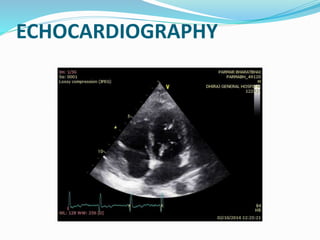

ECHOCARDIOGRAPHY

 2D echo:

 Pericardial thickening (TEE more sensitive)

 Normal RV and LV chamber size

 LA and RA enlargement

 Abnormal septal and posterior wall motion

 Paradoxical septal motion

 Premature opening of the pulmonic valve

 Dilated IVC without respiratory variation